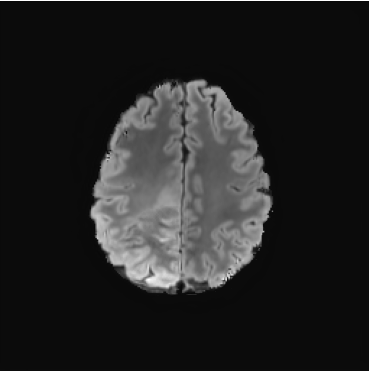

We also test our approach on healthy samples. Ideally, we would like our generative process to act as the identity function when given a normal image as input. Some examples are shown in Figure 6, where we can observe that the changes introduced by our sampling technique are relatively minimal and Dif-fuse preserves the structure and general appearance of the images.